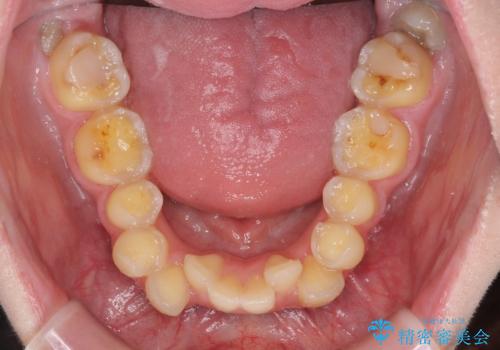

- 一時期の拒食症に伴い歯が酸で溶けてボロボロになってしまったとのことで来院された患者様です。

酸によりエナメル質の大半が溶けており、下顎前歯以外は酷いむし歯のような状態でした。